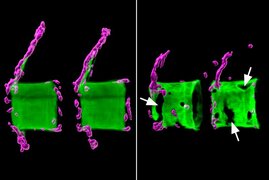

Wenn Chlamydien sich in der Zelle eines Menschen vermehren wollen, brauchen sie als erstes viel Glutamin. Ein Würzburger Forschungsteam hat geklärt,…